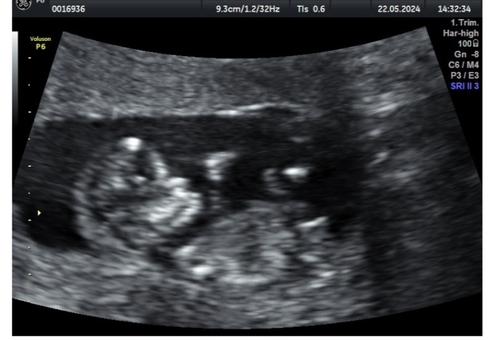

Vroeg meisje met nog een klein beetje tijd om te stijgen naar jongen, al verwacht ik niet meer dat het gaat stijgen, maar je weet nooit!

Ik denk een meisje maar niet heel duidelijk . 🩷

Meisje 🩷

Meisje